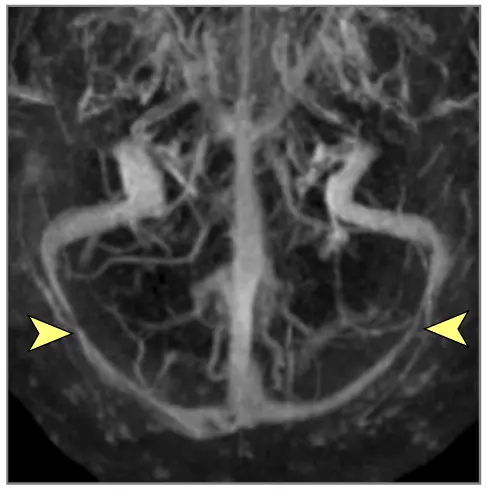

| დურალური ვენური სინუსის თრომბოზი (DVST) | ხშირად ძლიერი თავის ტკივილი (შეუძლია მიბაძოს IIH ან შაკიკი). კრუნჩხვები, კეროვანი დეფიციტები (ვენური ინფარქტების/სისხლჩაქცევის გამო), პაპილედემა/აწეული ICP ნიშნები ხშირია. რისკ-ფაქტორები ხშირად არსებობს (პროთრომბოტული მდგომარეობა, ორსულობა, ინფექცია, დეჰიდრატაცია). | MR ვენოგრაფია (MRV) ან CT ვენოგრაფია (CTV) ადასტურებს ნაკადის / თრომბის ("შევსების დეფექტი") ნაკლებობას დურალურ სინუსებში ან კორტიკალურ ვენებში. თავის ტვინის მრტ/კტ-მ შეიძლება აჩვენოს ვენური ინფარქტები (ხშირად ჰემორაგიული) ან შეშუპება. |

მრტ მიგნებები, რომლებიც მიუთითებს ინტრაკრანიალურ ჰიპერტენზიაზე (ხშირად ჩანს IIH-ში, მაგრამ შეიძლება მოხდეს ქრონიკული აწეული ICP-ის სხვა მიზეზებით) [9]:

- თავის ტვინის მრტ: სასურველი მოდალობა დეტალური ანატომიური შეფასებისთვის. შეუძლია აჩვენოს პარკუჭების გადიდება (ჰიდროცეფალია), გამოავლინოს ობსტრუქციული დაზიანებები (სიმსივნეები, კისტები, წყალსადენის სტენოზი), აჩვენოს მომატებული ICP-ის გართულებები (თიაქარი), აღმოაჩინოს კომუნიკაციური ჰიდროცეფალიის მიზეზები (მაგ., წინა სისხლჩაქცევის/ინფექციის ნიშნები), გამოავლინოს IIH-ის მიმანიშნებელი ნიშნები (ცარიელი კეხი, მხედველობის ნერვის გარსის გაფართოება, უკანა თვალის კაკლის გაბრტყელება, ვენური სინუსის სტენოზი MRV-ზე), ან აჩვენოს ცერებრალური შეშუპების გამომწვევი ძირითადი პათოლოგია (ინსულტი, სიმსივნე, ანთება) (7). სპეციფიკურ მიმდევრობებს (მაგ., CISS/FIESTA) შეუძლიათ შეაფასონ ლიკვორის ნაკადის დინამიკა.